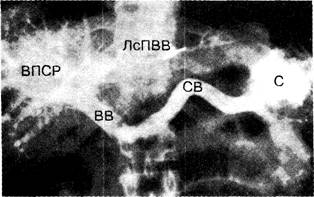

Нормальная ангиографическая картина ворот­ной вены при введении контрастного вещества с помощью чрескожной пункции селезёнки. Всё введённое контраст­ное вещество проходит через селезёночную и воротную вены в печень. С — часть контрастного вещества, задержавшаяся в селезёнке; СВ — селезёночная вена; ВВ — воротная вена; ЛсПВВ — левая сегментарная ветвь правой ветви воротной вены; ВПСР — внутрипеченочный сосудистый рисунок.